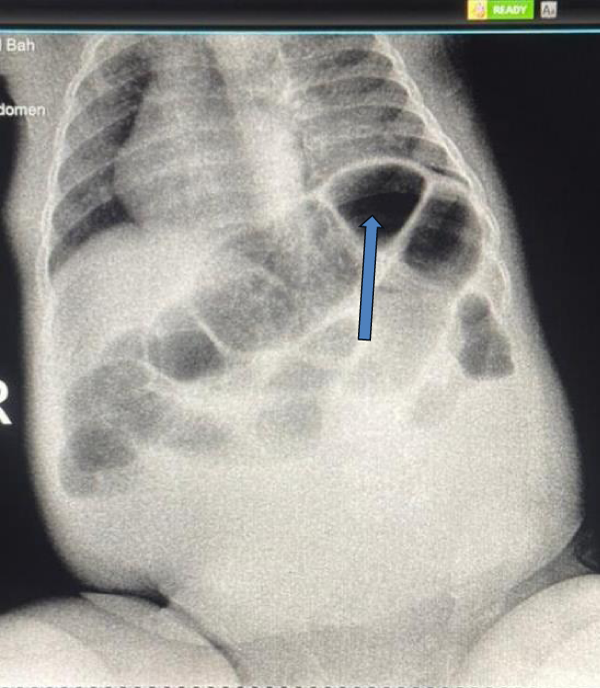

A stool examination revealed bloody stools by the third day of symptom onset. Laboratory results showed a leukocyte count of 6.8 × 109/L and hemoglobin of 7.8 g/dL (indicating moderate anemia). Mild hypokalemia of 3.06 mmol/L was noted, likely due to vomiting. A rapid point-of-care diagnostic test for Respiratory Syncytial Virus (RSV) was positive, confirming the viral etiology for the respiratory symptoms. Erect abdominal X-ray showed signs of intestinal obstruction, including dilated bowel loops and air-fluid levels, raising suspicion for intussusception (Figure 1). A diagnostic ultrasound confirmed the diagnosis.

Figure 1: Abdominal X-ray showing signs of intestinal obstruction (dilated bowel loops, air-fluid levels-arrow).